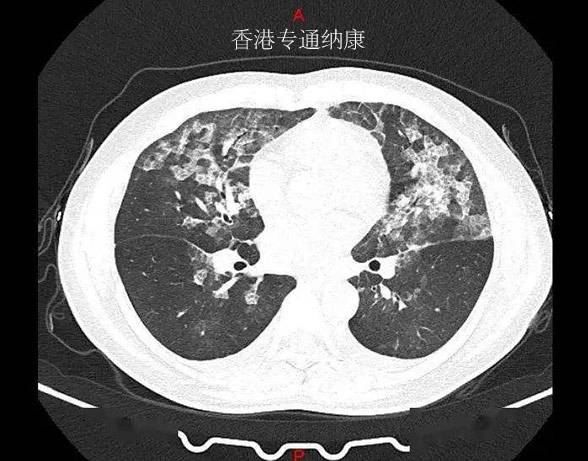

三、DS8201(Enhertu)肺癌治疗

客观缓解率92.3%,DS-8201引领肺癌靶向治疗掀起创新革命

去年ASCO大会上发布的DESTINY-Lung01研究是针对既往往接受过一种或多种系统治疗,出现疾病进展的HER2突变型(HER2m)不可切除和/或转移性非鳞非小细胞肺癌(NSCLC)患者展开的,其中大多数患者曾接受过含铂化疗(90.5%)和抗PD-1或PD-L1治疗(54.8%)等治疗。研究结果表明,接受DS-8201单药治疗(6.4mg/kg)的,61.9%的患者获得肿瘤缓解,疾病控制率(90.5%)和中位无进展生存期(14.0个月)得到显著改善。

在今年ESMO大会上进一步更新了数据,HER2突变型患者中,有1例患者达到完全缓解,49例达到部分缓解,疾病稳定者34例,疾病进展3例,4例无法评估,确认的客观缓解率达54.9%,疾病控制率高达92.3%!